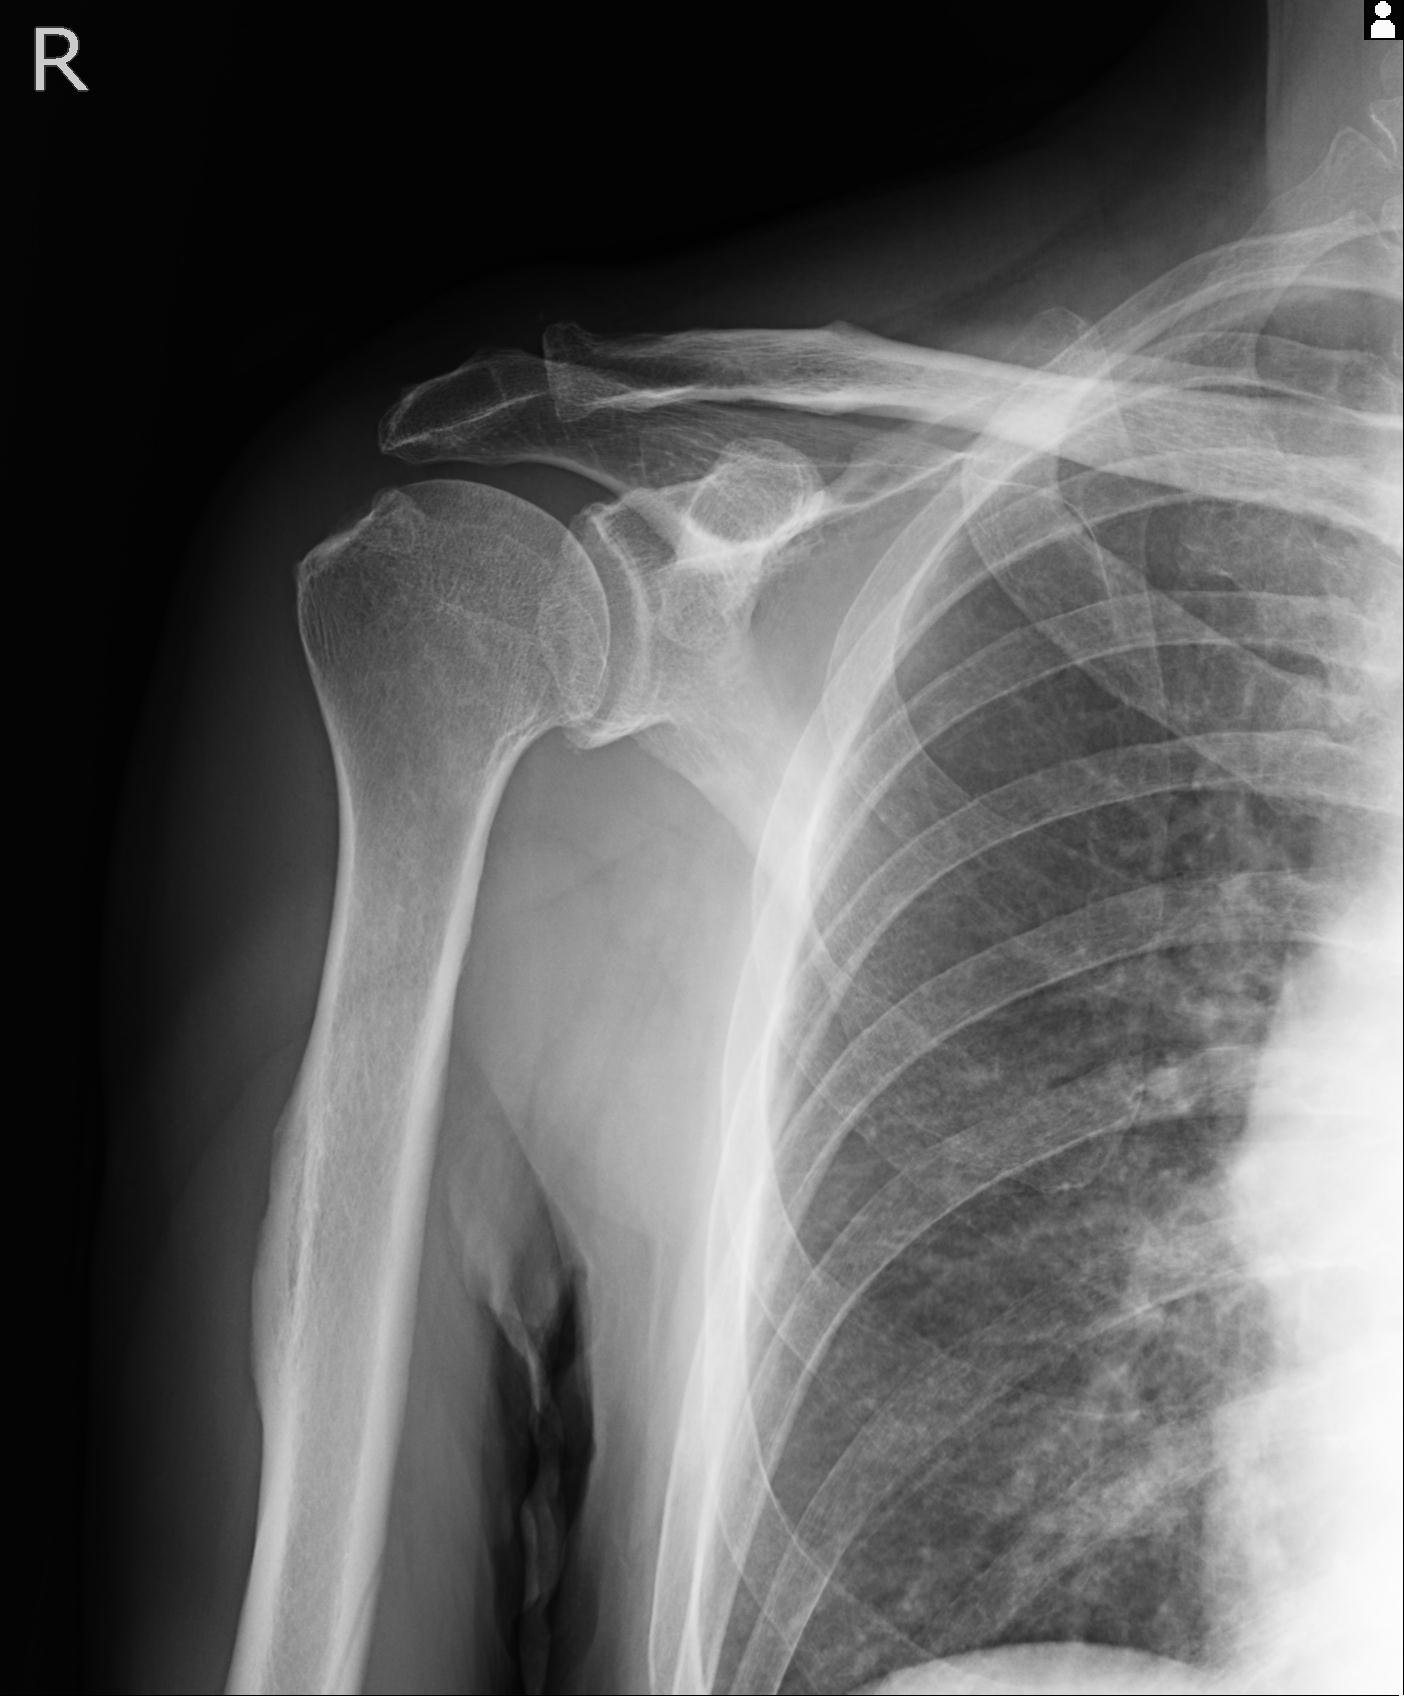

110214 12/20 肩 2R 12/21 肩 4R 72歳女性 左上腕外科頚プレート